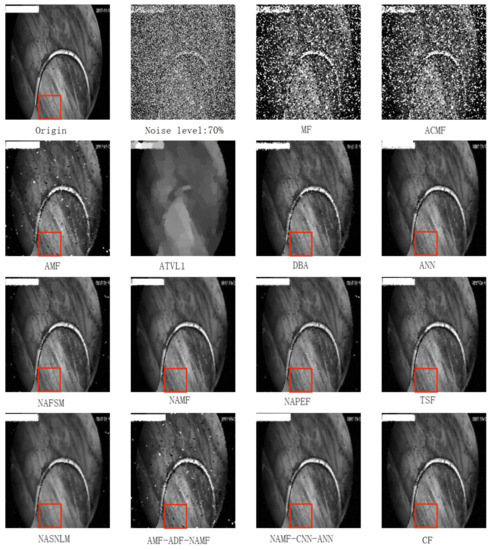

- To reduce the impact of salt and pepper noise on the object detection network, a salt and pepper noise reduction method based on edge feature preservation is proposed. Compared with fourteen other methods, this method has the highest peak signal-to-noise ratio. The proposed image denoising methods can improve the mAP of Faster R-CNN, YOLOv4, TOOD, SSD, and FSSD.

- The image with noise is denoised by AMF, NAMF, and ANN.

- Anisotropic diffusion fusion is used to combine the image denoising results of AMF, NAMF, and ANN in pairs.

- The noise reduction results of the three algorithms and the pin-two fusion results of the three algorithms are combined, then the maximum value of the combination according to the PSNR is used to obtain the final image denoising cascade optimization results.